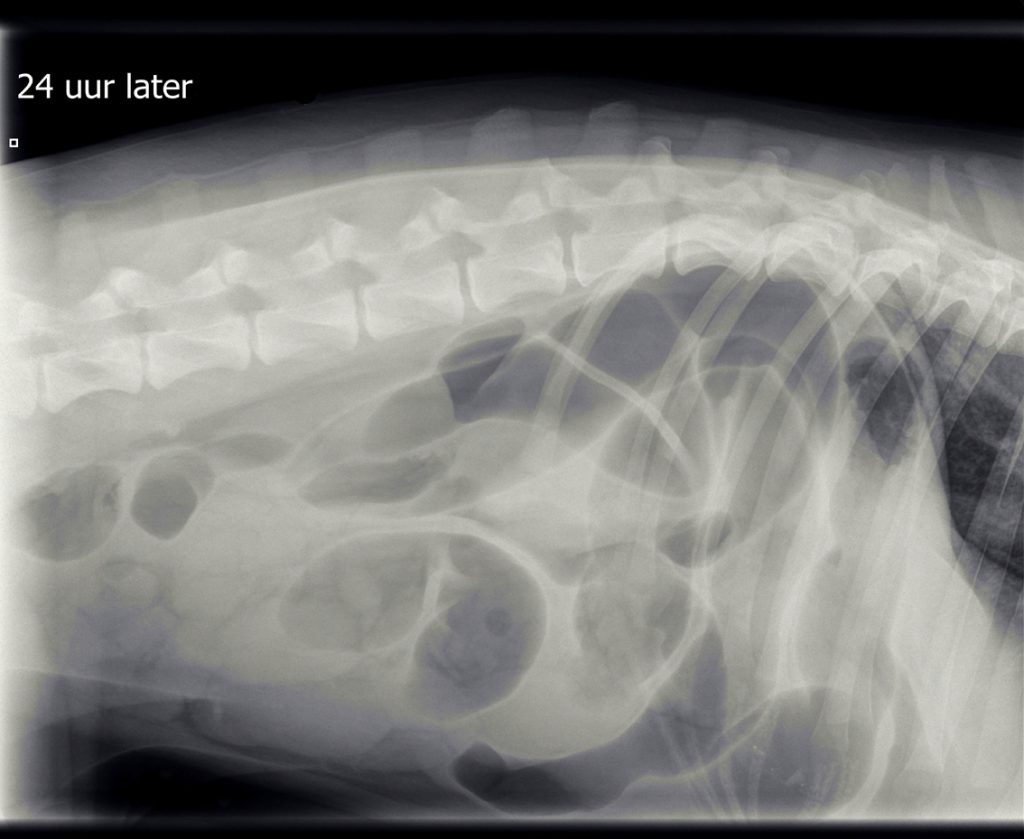

Omdat de hond verder niet ziek was en de buik niet gevoelig, werd besloten om de röntgenfoto’s na een dag te herhalen. Hierop was er geheel geen verbetering zichtbaar in de buik ten opzichte van de dag ervoor.

De hoeveelheid lucht had zich zelfs vermeerderd, wat meer in de richting van een verstopping wees, mogelijk door een vreemd voorwerp. De eigenaren vertelden dat er een latex koetje vermist werd. Helaas is latex meestal niet zichtbaar op een röntgenfoto. De enige mogelijkheid om een verstopping te verhelpen die niet reageert op medicatie, is opereren, dus diezelfde middag werd T-Bone voorbereid voor operatie.